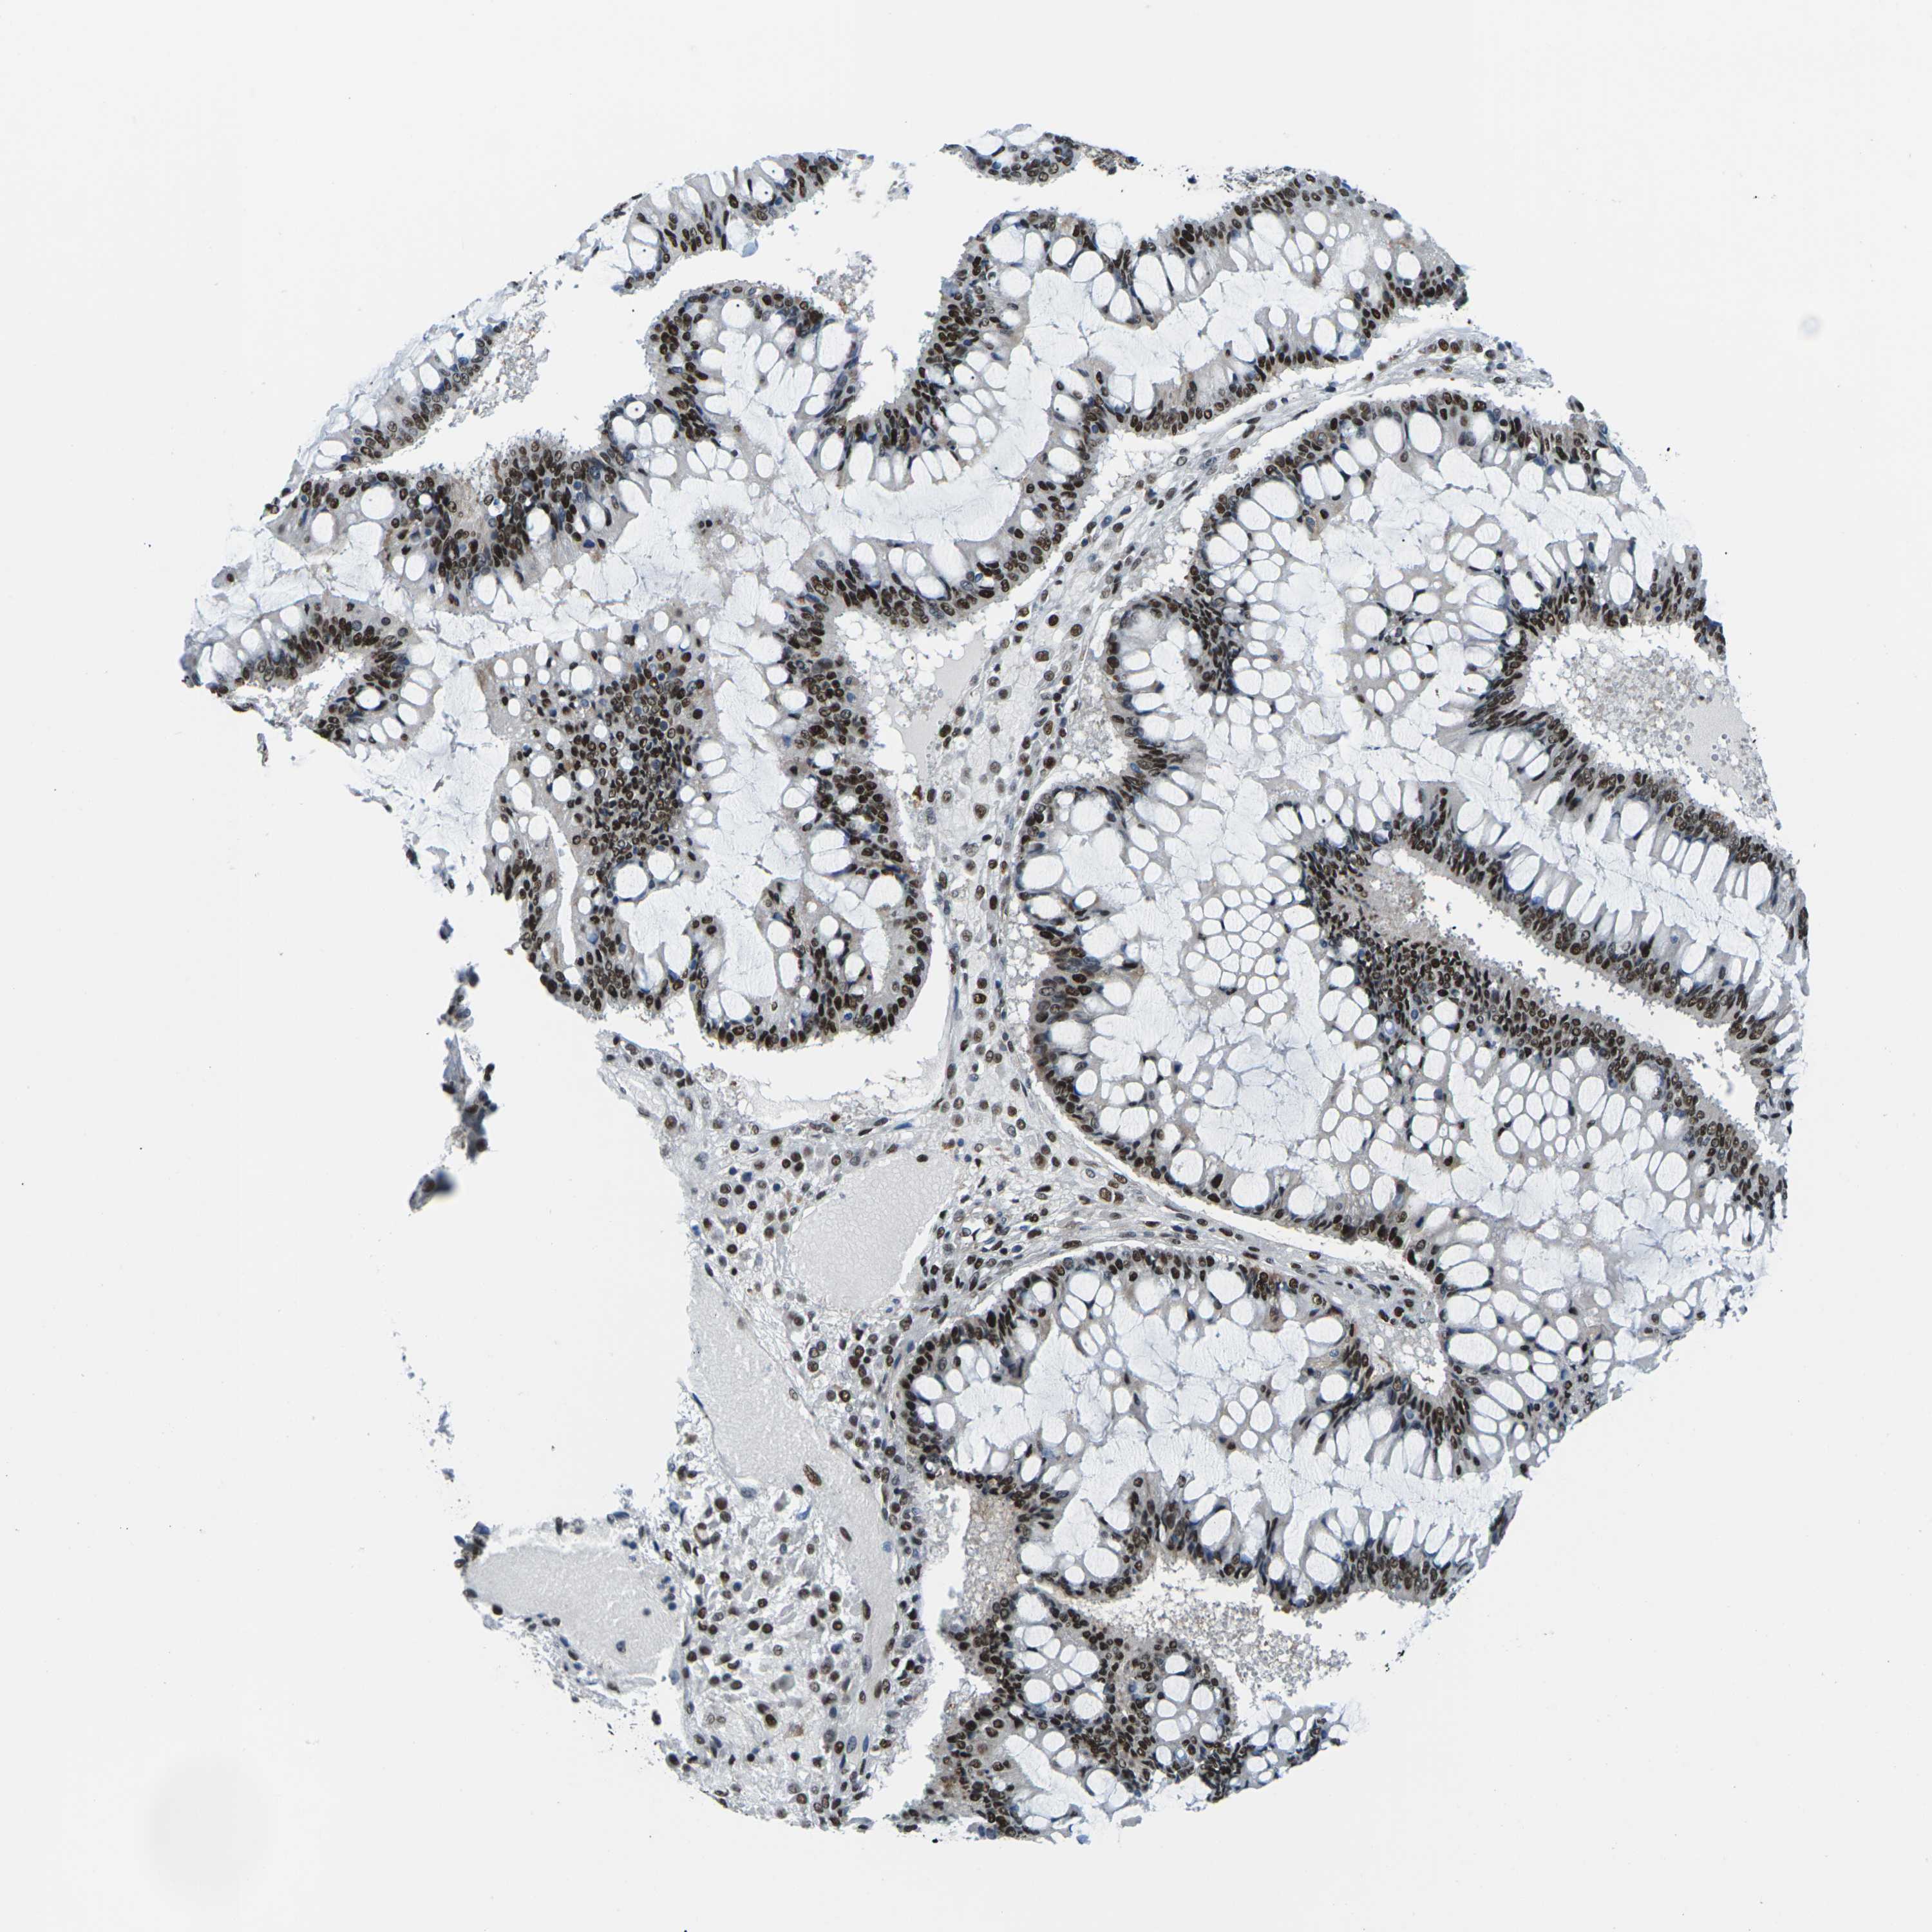

OVARIAN CANCER - Protein expressioni

A mouse-over function shows sample information and annotation data. Click on an image to view it in a full screen mode. Samples can be filtered based on level of antibody staining by selecting one or several of the following categories: high, medium, low and not detected. The assay and annotation is described here.

Note that samples used for immunohistochemistry by the Human Protein Atlas do not correspond to samples in the TCGA dataset.

Antibody stainingi

Antibody staining in the annotated cell types in the current human tissue is reported as not detected, low, medium, or high, based on conventional immunohistochemistry profiling in selected tissues. This score is based on the combination of the staining intensity and fraction of stained cells.

Each image is clickable and will lead to virtual microscopy that enables deeper exploration of all samples and also displays staining intensity scores, fraction scores and subcellular localization as well as patient and tissue information for each sample.

Antibody HPA012510

Antibody CAB008388

Cystadenocarcinoma, serous, NOS

Carcinoma, endometroid

Cystadenocarcinoma, mucinous, NOS

Carcinoma, NOS